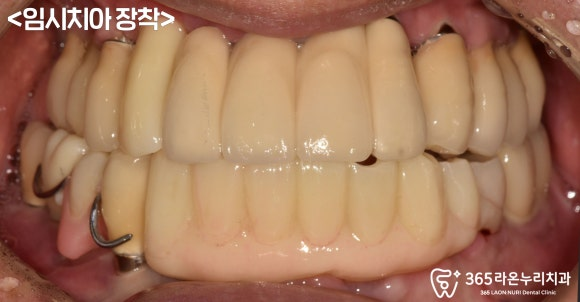

■ 5. 임시치아 제작

이 케이스에서는

워낙 염증이 심하고 뼈도 많이 없으셔서

인공뼈를 이식한 뒤 기다리셔야 됐는데요,

그 사이에 사용하실

임시치아 제작 과정을 설명드리겠습니다.

픽스처를 심은 당일에

그 위로 바로 어버트먼트를 연결해 드렸고

그 위로 임시치아까지

올려드렸습니다.

주변 자연치와 유사한 색으로

자연스럽게 만들어드렸으며

위쪽(교합면)에서 바라보면

이렇게 보이는데

이전의 플리퍼와 달리

어버트먼트에 살짝 기대어 올려드렸기에

훨씬 더 고정력이 있고 편하실 겁니다.